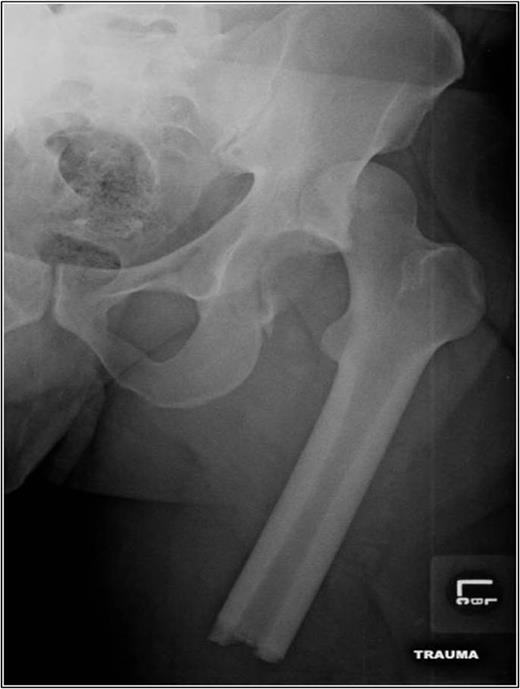

Operative management focused on closed reduction of the dislocated left hip. Two 5.0 mm Schanz pins with a carbon fiber bar (Zimmer, Warsaw, Indiana, USA) were placed in the proximal femur fragment. This was used to aid with the closed reduction maneuver of knee flexion, hip traction, adduction and internal rotation. Confirmed by intra-operative fluoroscopy, the femoral head was irreducible due to the engaging femoral head lesion on the acetabulum. A conversion to open reduction via a Kocher–Langenbeck approach in the lateral position ensued. The femoral head and posterior wall were reduced under direct visualization with two 3.5 mm pelvic reconstruction plates (Zimmer). The patient was moved to the supine position and underwent definitive femoral fixation with a retrograde, reamed femoral nail (Zimmer). Thigh compartments at the conclusion of the femoral fixation were tense and non-compressible, requiring a thigh compartment fasciotomy. Negative pressure therapy was placed over the incision and the knee laceration was primarily closed. After multiple washouts of his lateral fasciotomy incision, he was primarily closed 1 week after initial presentation. He was discharged non-weight bearing on his left lower extremity on post-operative day 22. Eleven months post-injury, he remains full weight bearing without assistance. He reports intermittent pain with ambulation and radiographs show early arthritic changes and heterotopic ossification of his left hip (Fig. 4).

AP pelvis 8 months status post-ORIF of posterior wall with retrograde femoral nail. The left hip demonstrates early post traumatic arthritis and heterotopic ossification.